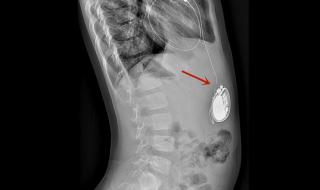

一、全磁浮人工心脏介绍

全磁浮心脏即离心泵人工心脏,被称为第三代人工心脏,是目前最先进,对人体影响最小也是最耐用的人工心脏,美国FDA前两年刚上市了第一款,我国高端医疗器械几乎无国产产品。